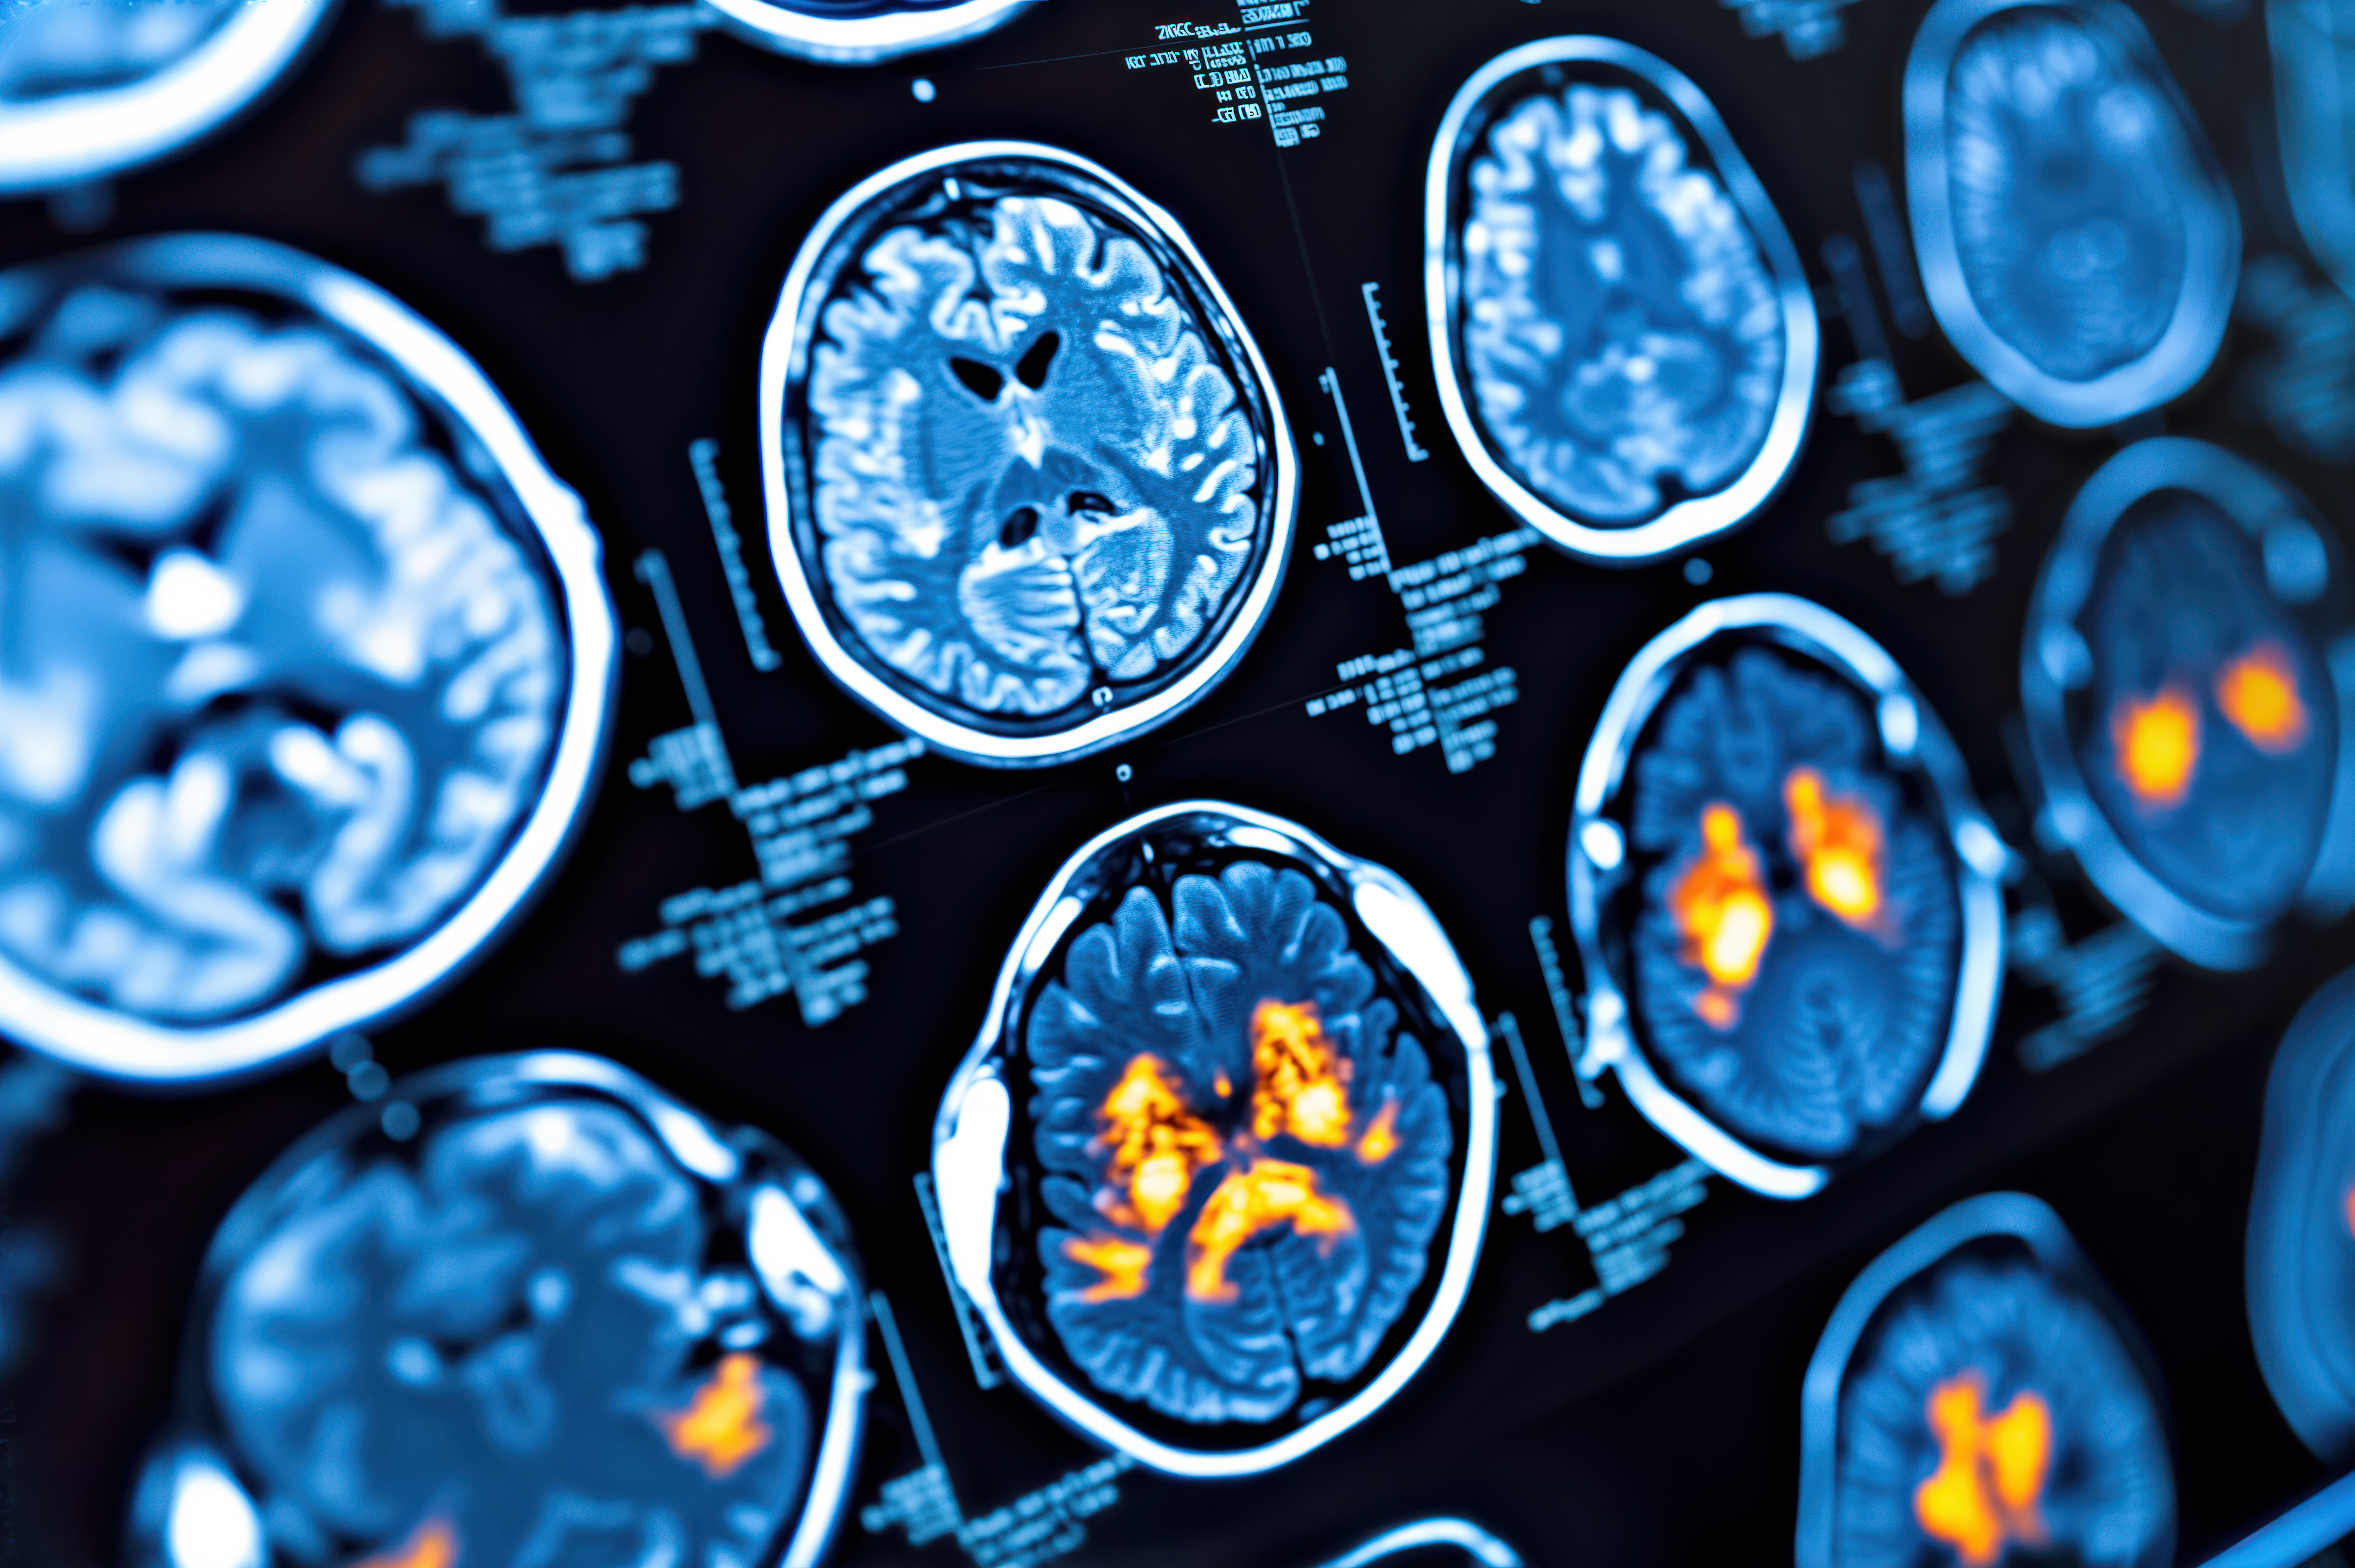

Initial findings from the Anti-Amyloid Treatment in Asymptomatic Alzheimer's Disease (A4) study, published online April 6 in JAMA Neurology, have confirmed that high levels of amyloid on florbetapir-PET brain scans are an indication of cognitive decline.

This portion of the A4 study included 4,486 eligible participants (mean age, 71.3 ± 4.7 years) who underwent amyloid-PET imaging with florbetapir (Amyvid, Avid Radiopharmaceuticals). Standardized uptake value ratios (SUVr) between 1.10 and 1.15 were considered indicative of elevated amyloid levels. The researchers also compared, among other key characteristics, the subjects' demographic data, family history, and the presence of the dementia-contributing apolipoprotein E (APOE) ε4 genotype.

Florbetapir-PET revealed 1,323 people (29%) who were positive for beta-amyloid accumulation, compared with 3,163 beta-amyloid-negative subjects (70%). The beta-amyloid-positive participants also were significantly older, had a history of family dementia, and showed at least one APOE ε4 genotype.